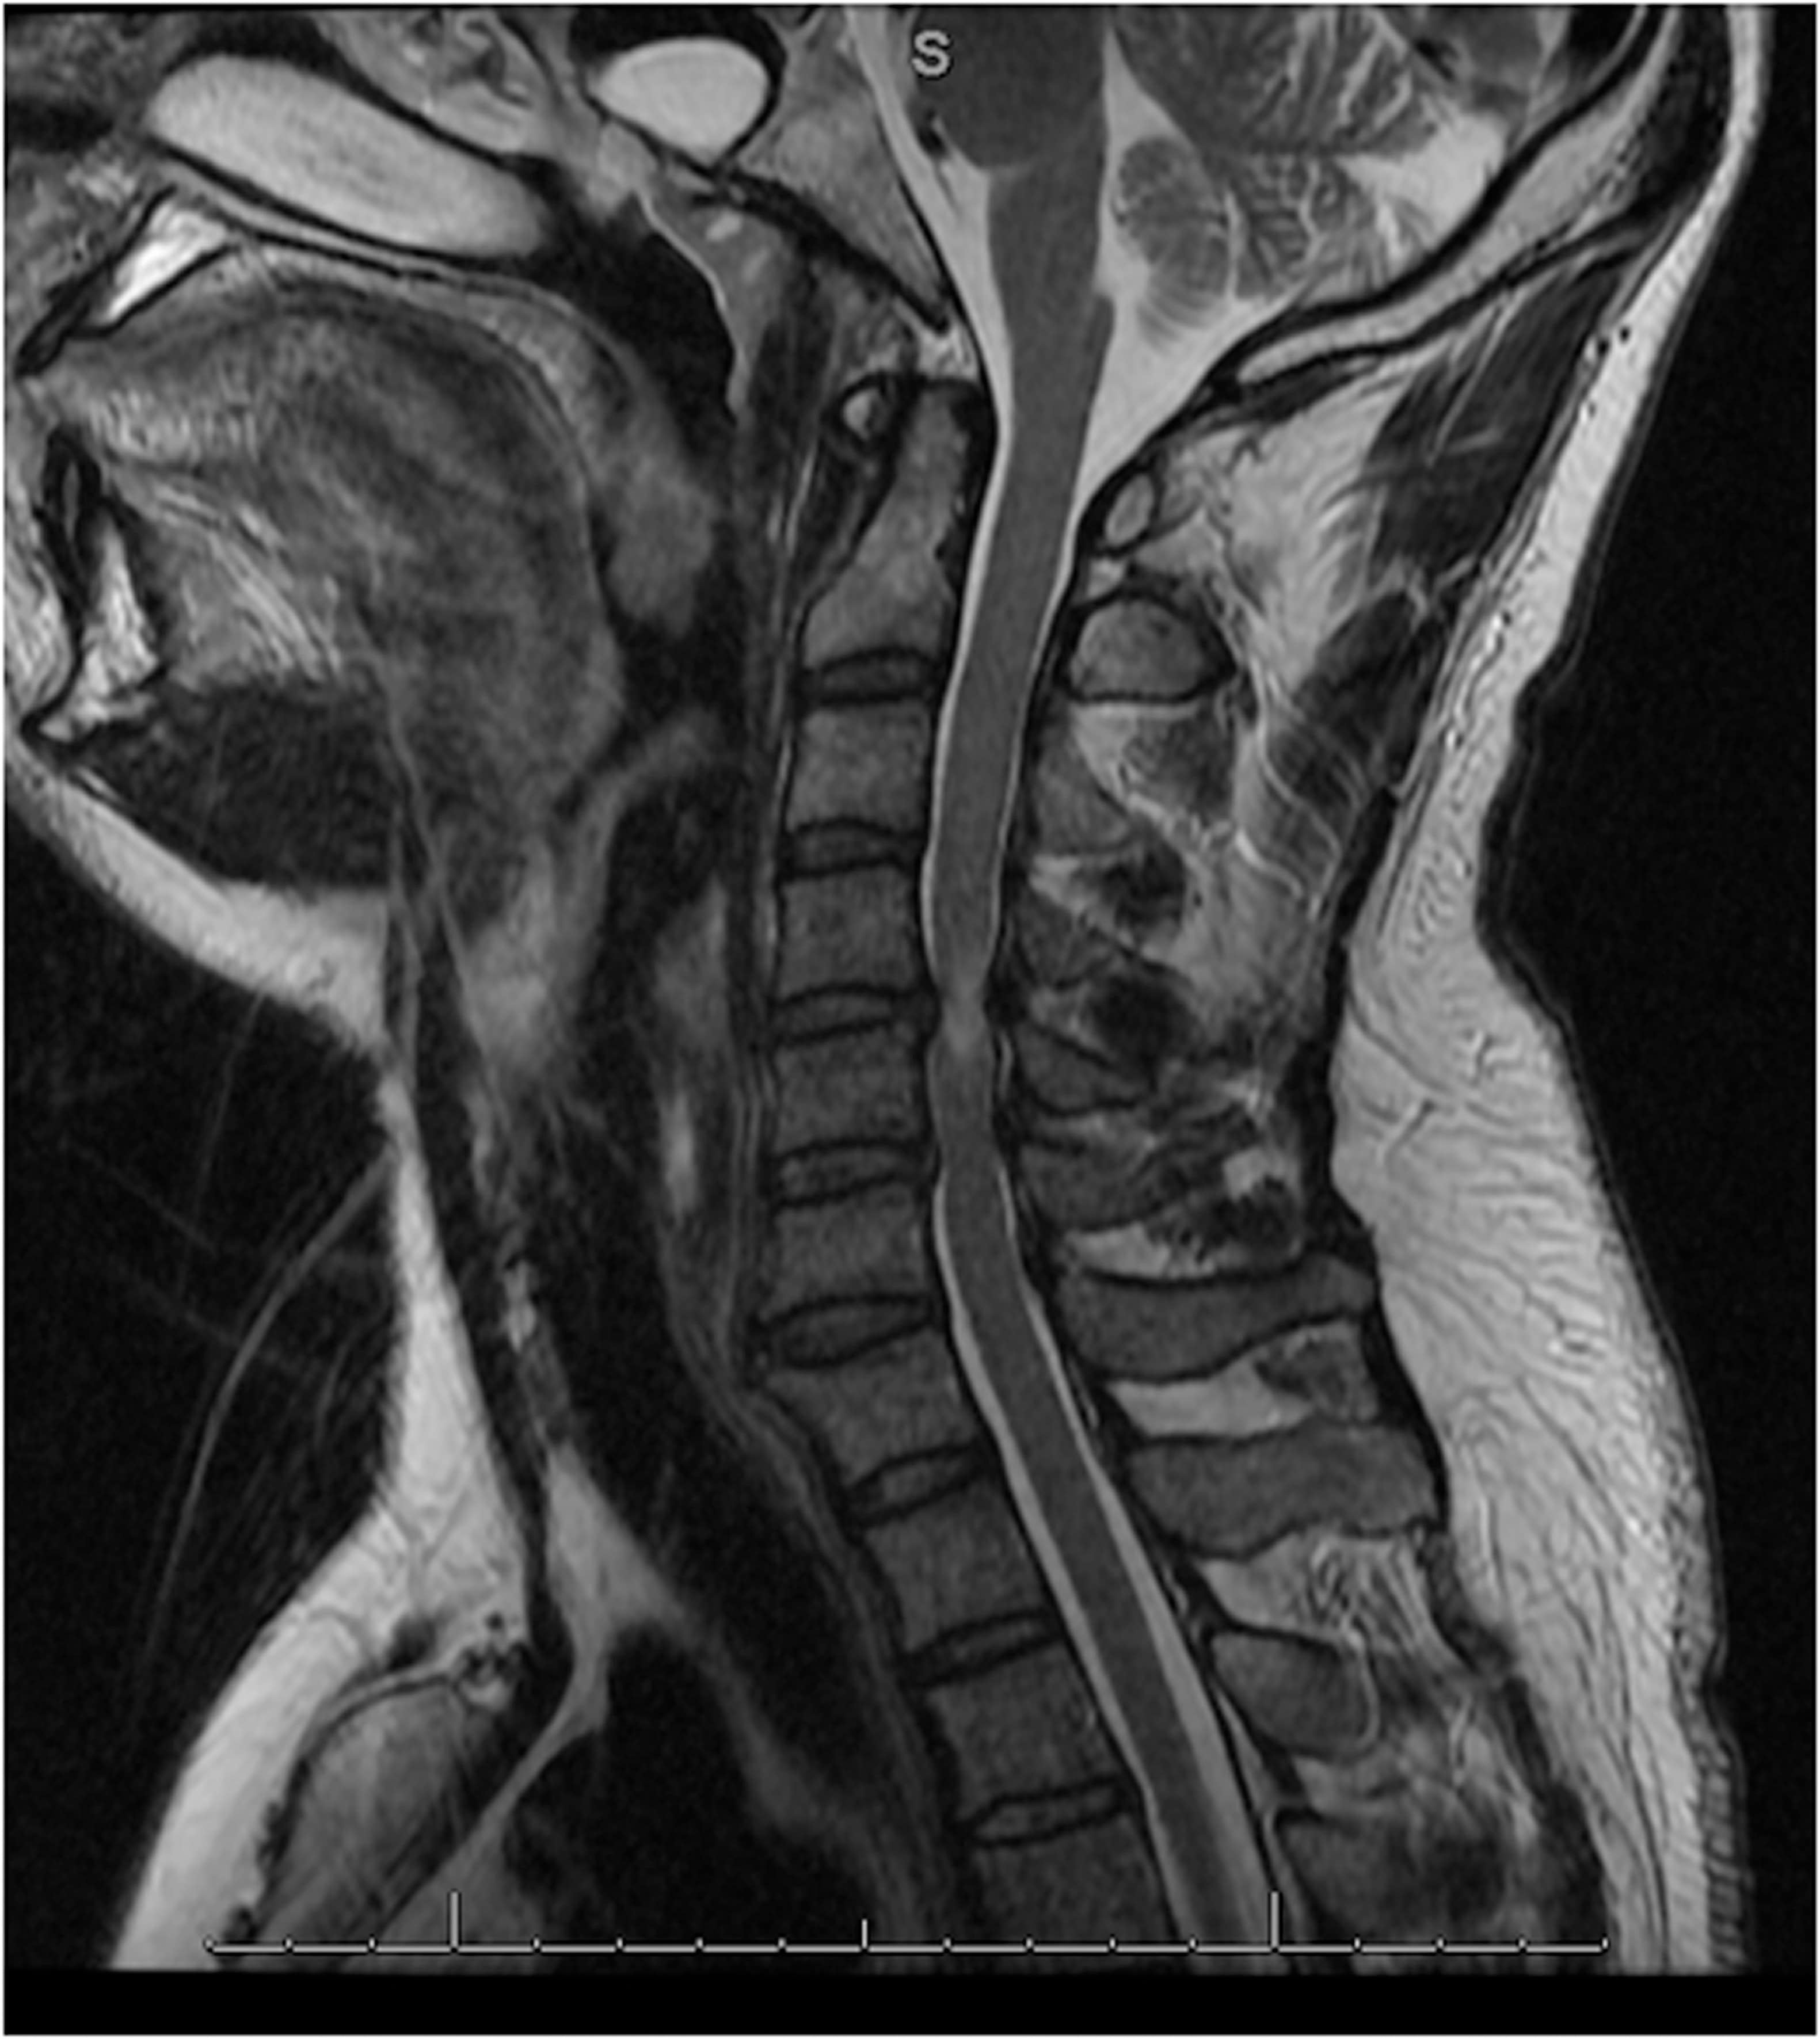

Image Results

Cervical Spinal Stenosis